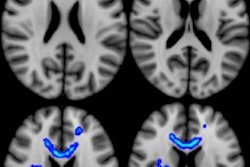

One month after injury, fMRI showed hyperactivation during memory tests in the right precuneus (p = 0.047) and right inferior parietal gyrus (p = 0.025) in younger patients with mild TBI, compared with their control counterparts. Among the older mildly concussed subjects, hypoactivation was found in the right precuneus (p = 0.013) and right inferior frontal gyrus (p = 0.019) during their memory tasks, compared with the older control group.

Images show different working memory activation patterns in healthy control subjects and young and old patients with mild TBI. Young control subjects (top left) had increased activation in the frontal and parietal regions, predominantly at the left hemisphere. In the initial exam, young patients with TBI (top middle) had bilateral hyperactivation in the frontal and parietal regions, compared with young control subjects. Partial recovery of the activation pattern (top right) is seen at follow-up imaging. Older control subjects (bottom left) had increased cerebral activation in bilateral frontal and parietal regions. In the initial exam, older TBI patients (bottom middle) showed hypoactivation, compared with the older control subjects. The older TBI patients had even less activation at follow-up (bottom right). Image courtesy of RSNA.Follow-up scans